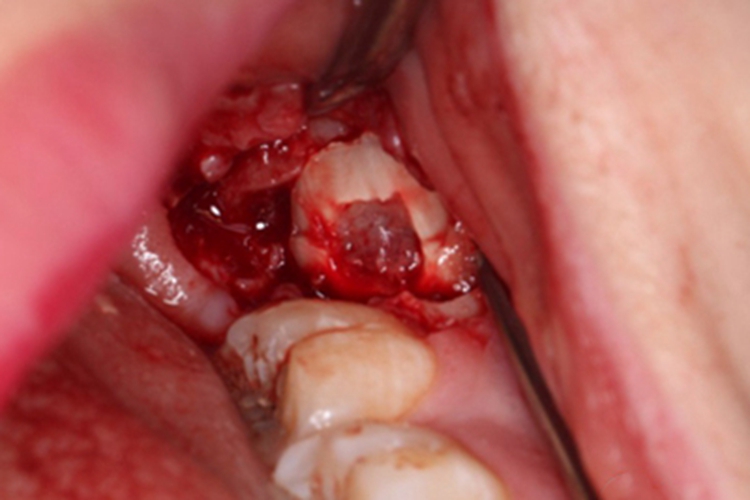

缝合

将阻生牙拔除后认真清理干净牙槽窝,如有炎性肉芽组织、牙囊肿等异常组织,应予以刮除,再将游离的牙龈缘或翻开的黏骨膜瓣进行缝合,使组织复位,以缩小创口,保护血凝块,防止术后出血,有利于创口愈合。